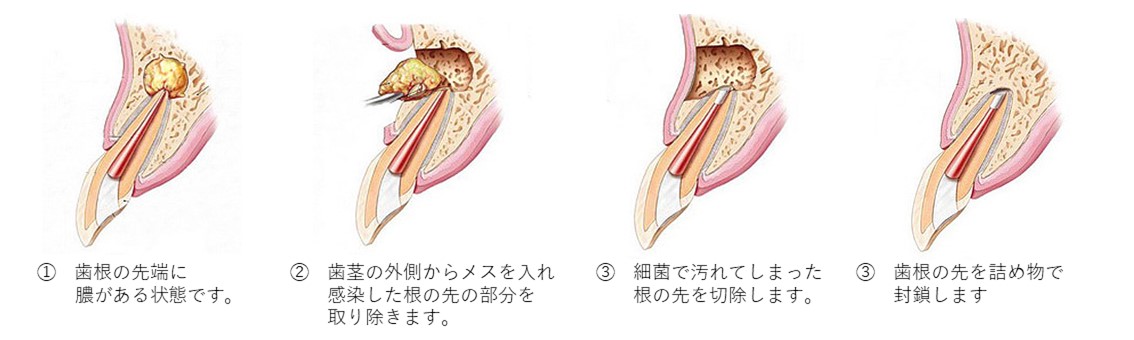

歯根端切除術(しこんたんせつじょじゅつ)

根の先に溜まった膿の袋(根尖病変)が大きく、通常の治療では治りきらない場合、歯ぐき側からアプローチして根の先を数ミリ切除し、病巣を直接取り除く手術です。

口腔外科出身の技術が最も活きる治療の一つです。